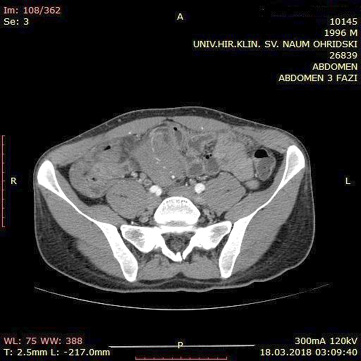

A contrast enhanced CT scan was indicated due to the palpable abdominal tumor and it revealed a formation that originates from the ileal mesentery involving the ileocolic artery and a part of the ileum with ileal wall thickening and partial obstruction (Figures 2, 3 and 4).

24.jpg Figure 2 23.jpg Figure 3

25.jpg Figure 4